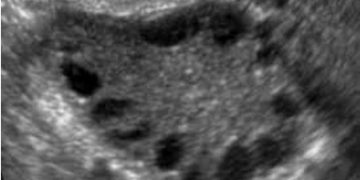

Leggi di piùCari colleghi, vi presentiamo la guida al counseling di Marzo 2025 sulla PCOS!! Potrete scaricarla cliccando sul link. Grazie a Mara Albanese! ...